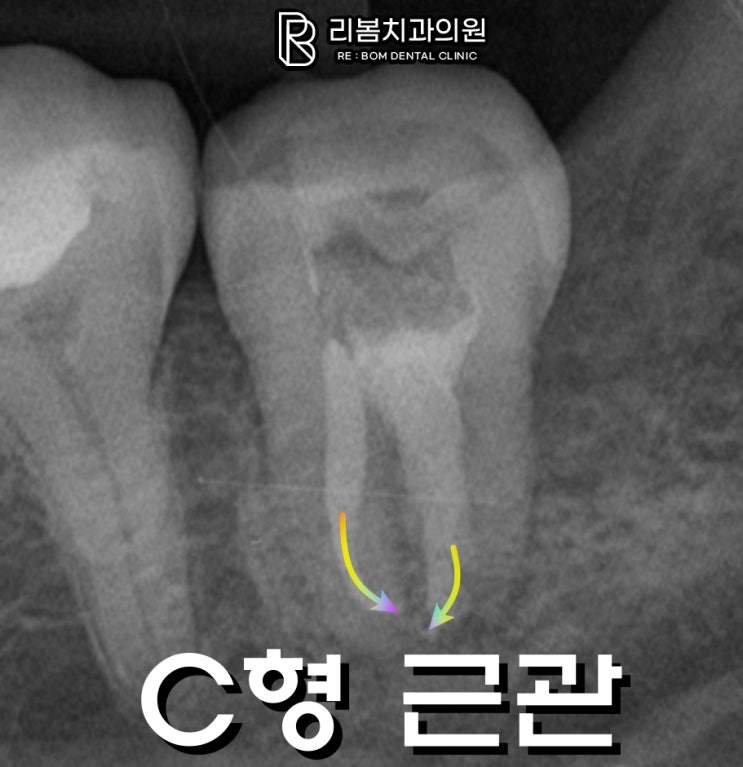

송도 치과 C-canal 구부러진 근관 신경 치료가 어려운 이유

송도 리봄의 박현호 원장입니다. 치과 진료 중 근관 치료는 환자 입장에서 그 중요성에 비해 과정이 잘 보...